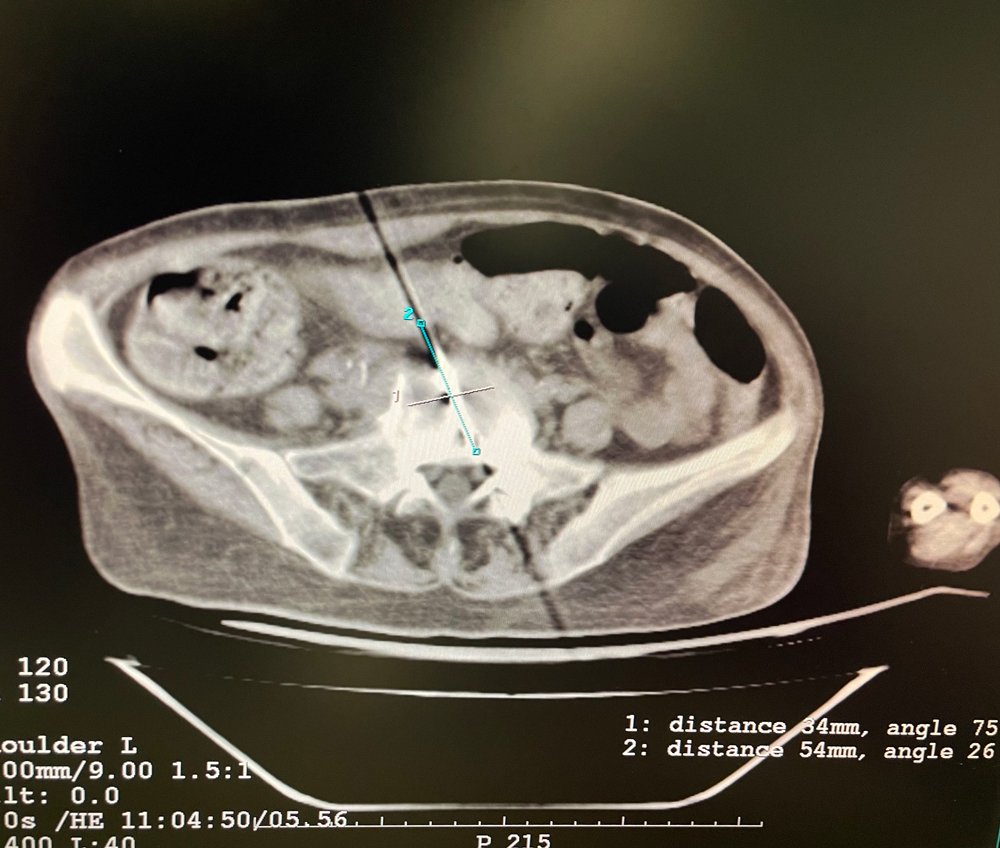

患者一

女,56岁,肺转移瘤,骶骨、左侧肋骨各一转移灶,病灶大小均为5cm。骶骨转移灶、肋骨转移灶各进行2个冻融循环。患者术后状况良好。